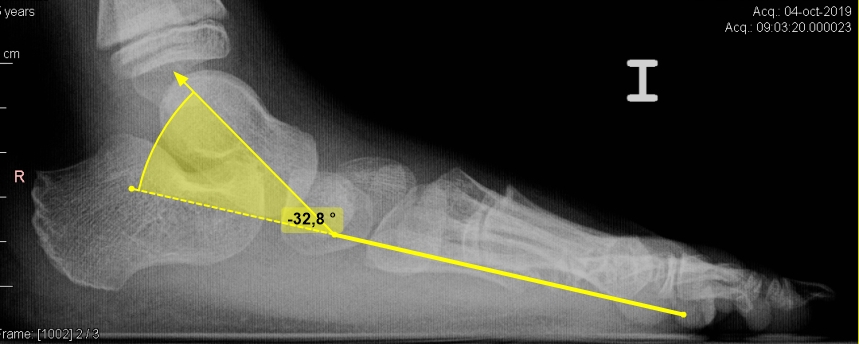

La primera técnica de imagen debe ser la radiografía convencional. Estas pueden objetivar un “os trigonum”, un proceso posterior del astrágalo hipertrófico, una fractura o una pseudoartrosis de la cola del astrágalo.